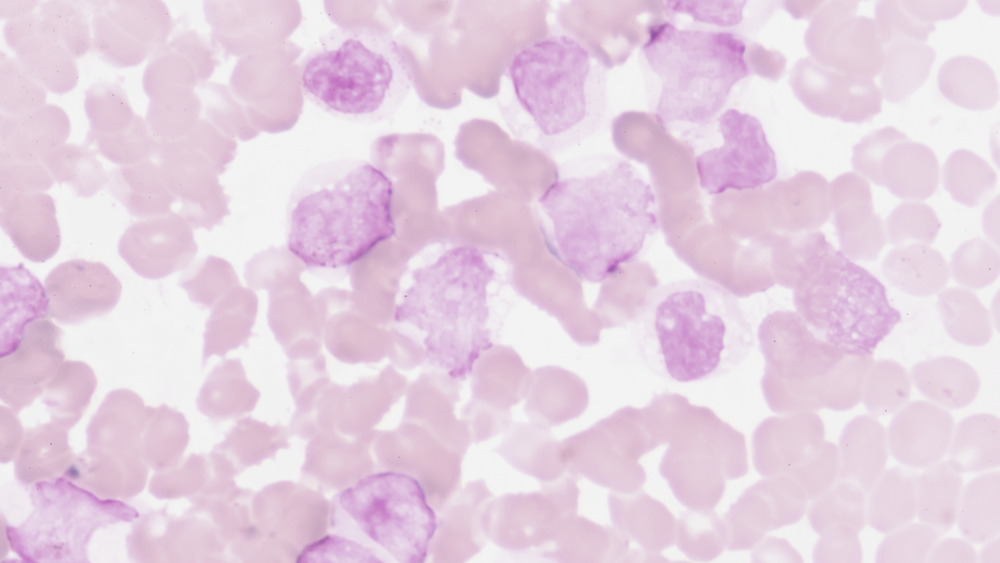

Острые лейкозы

Острые лейкозы развиваются стремительно, в крови человека за короткий срок концентрируется большое количество атипичных клеток.